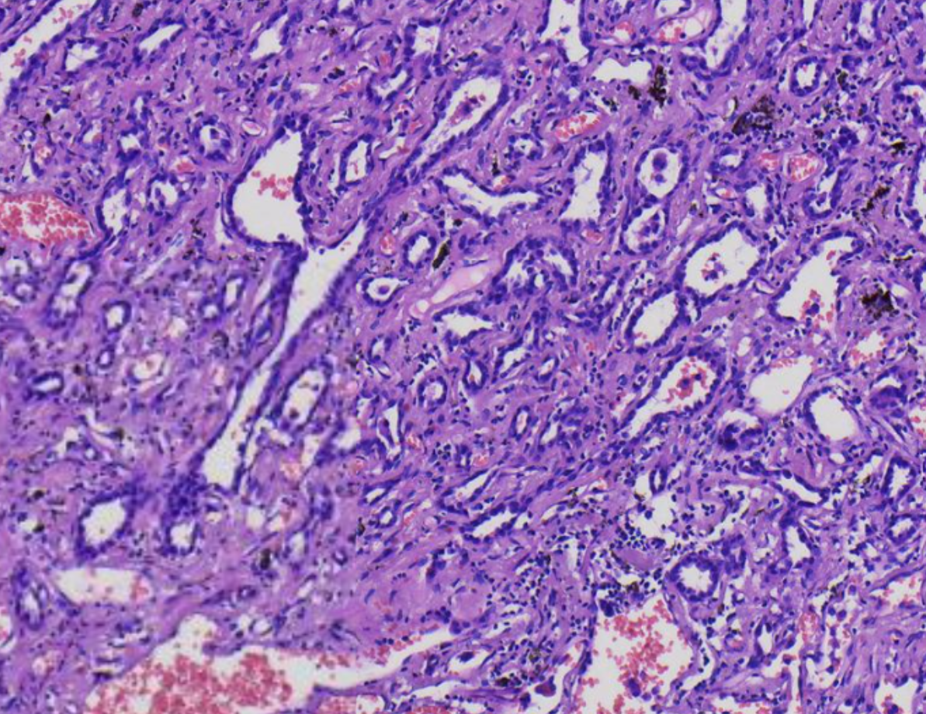

HE诊断思路

肿瘤均由腺泡结构组成

局灶可见腺上皮呈鞋钉样改变

腺泡间间质增宽

部分腺泡腔内见巨噬细胞

未见明显的双层细胞